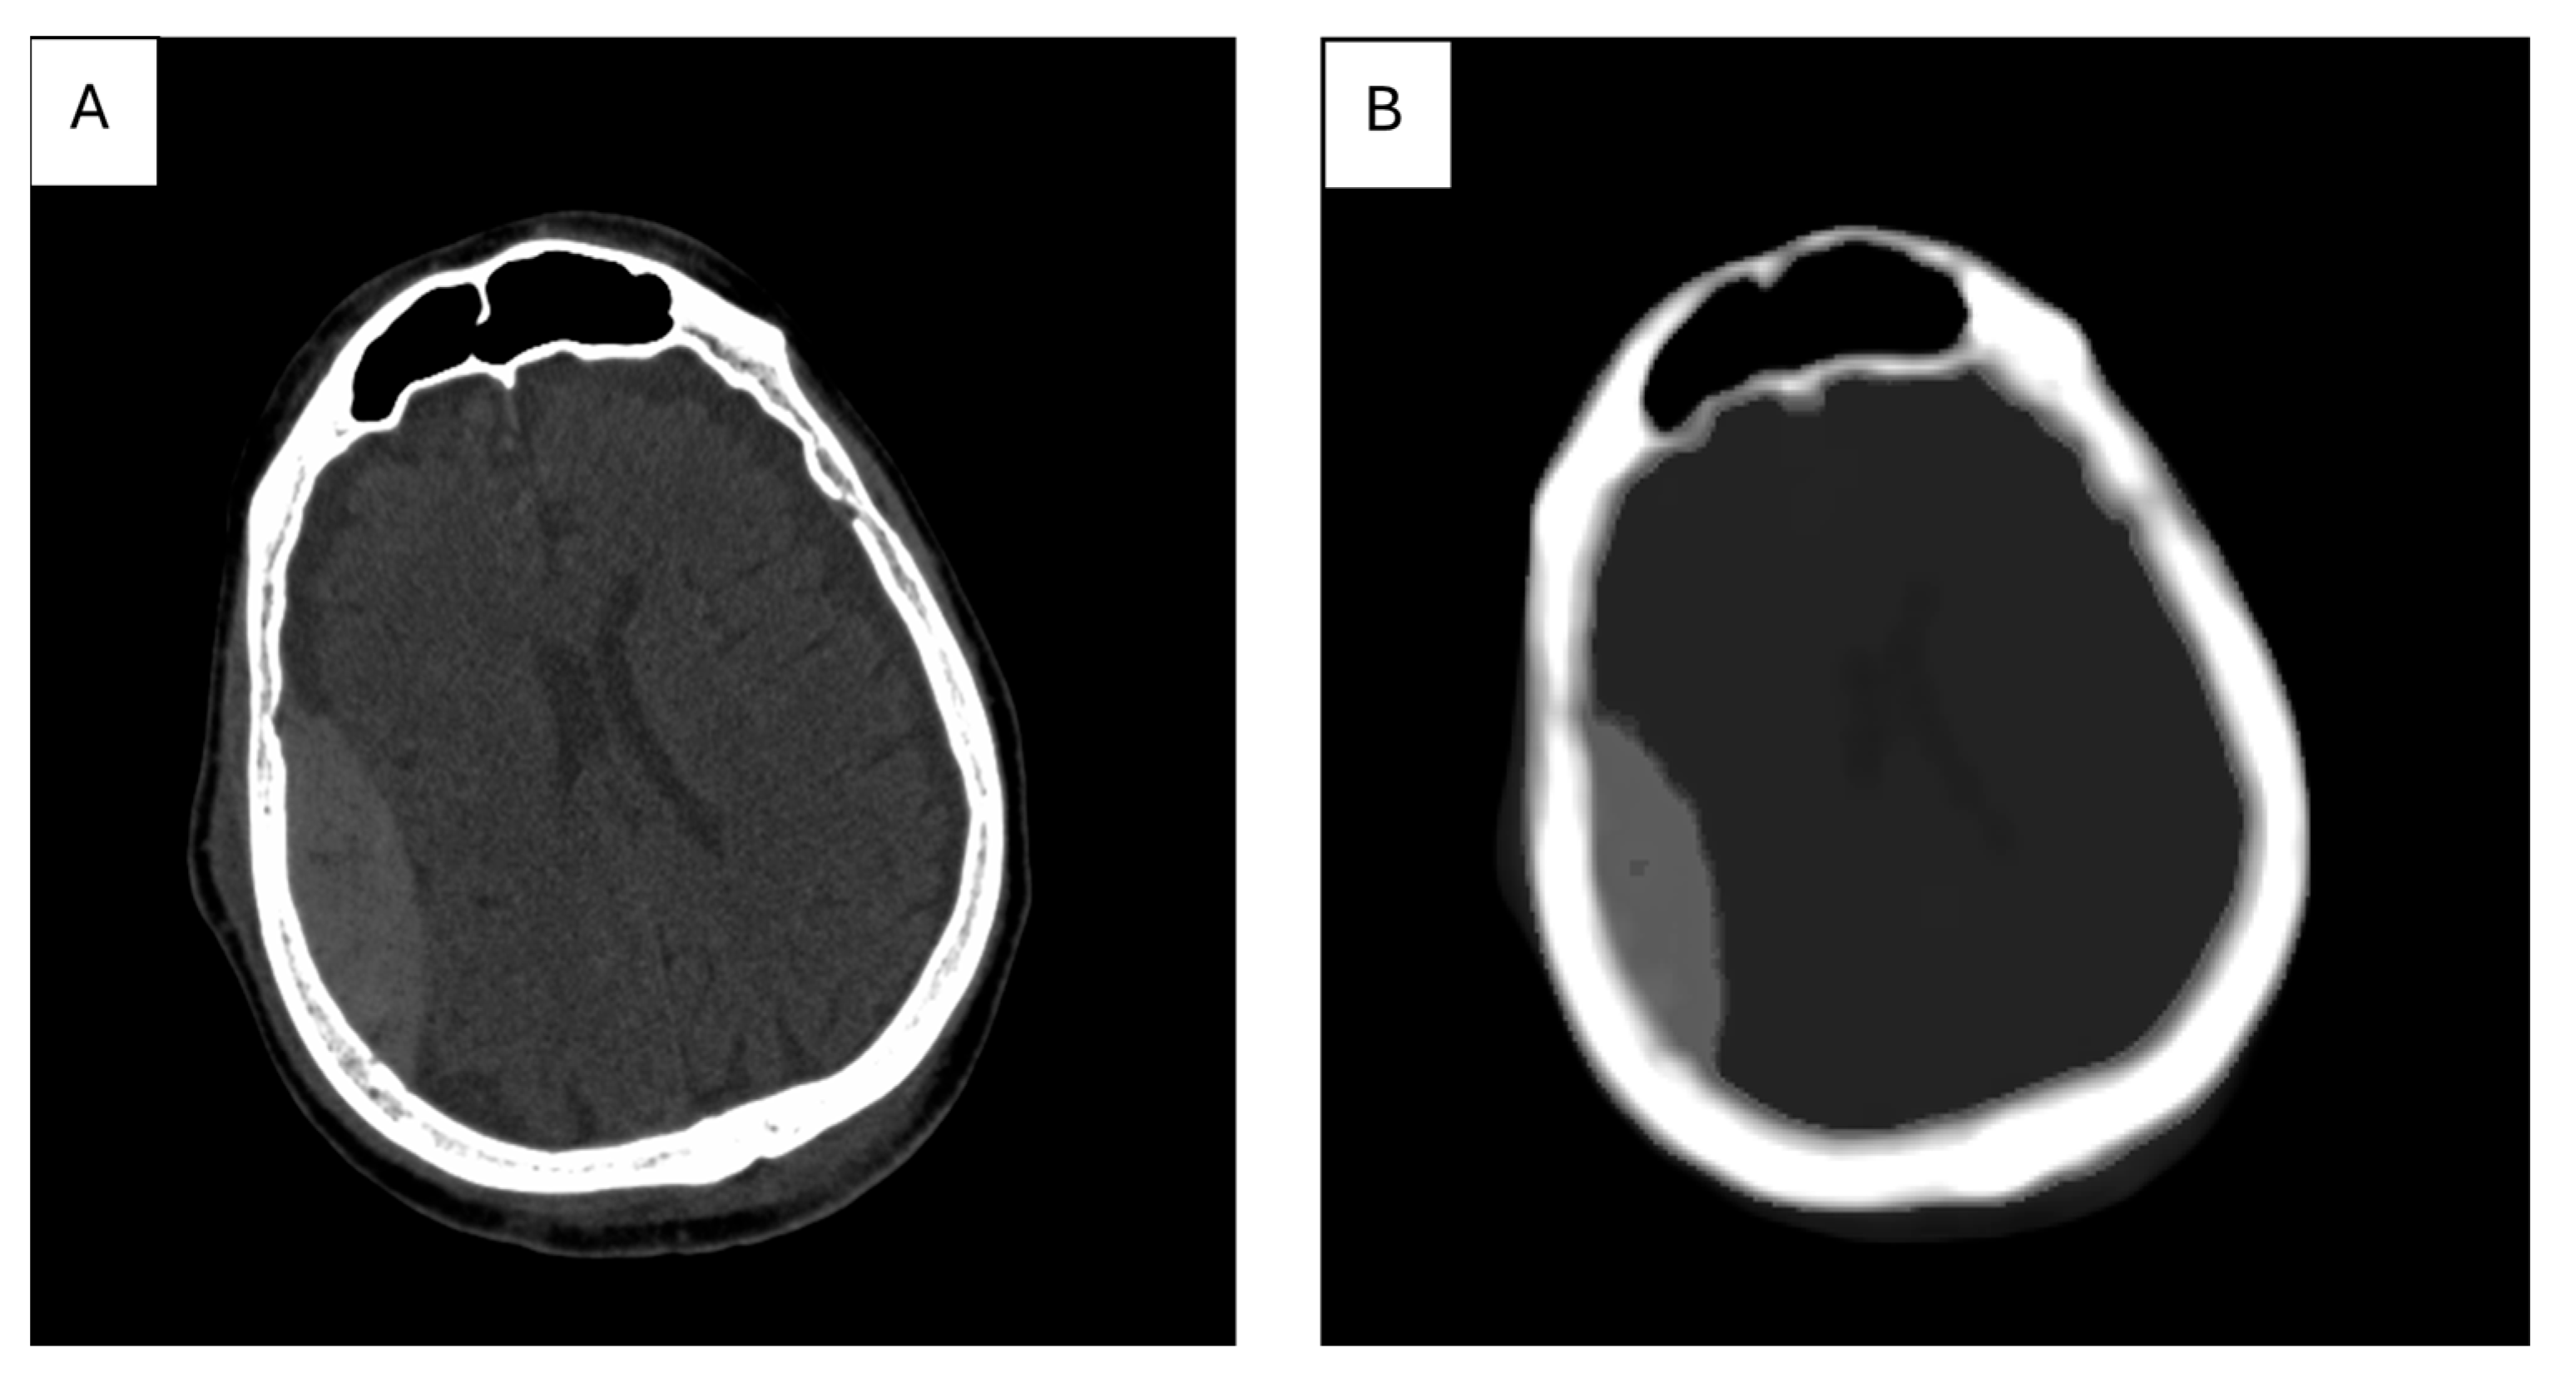

The map—or, more often, maps—of features selected during the selection process are used as input data for the segmentation stage. An example feature map for an image of a brain cross-section, containing a fragment of a subarachnoid hemorrhage, is shown in Figure 4 where the map of the AngularSecondMoment feature (calculated based on the Gray Level Cooccurrence Matrix, GLCM) [104] contains the stroke area, which has a significantly different value than the rest of the brain; therefore, the image of this map allows us to isolate the stroke area using simple brightness thresholding.

Figure 4.

CT image of a brain cross-section with a marked stroke area (A); AngularSecondMoment feature map calculated for this image, in which a 15 × 15-pixel window was used (B).